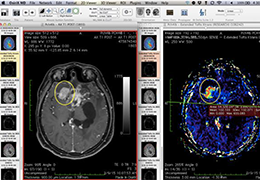

成像智能。

Eclipse 成像智能功能提供强大的处理能力和最佳质量的影像,同时减少质量错误并提高剂量效率。

凭借 AI、专有算法和先进的影像处理能力,提供出色的影像质量和无与伦比的诊断信心。

与标准影像处理相比,智能降噪功能可使客户降低辐射剂量,而不会损失影像质量。这在新生儿和儿科成像中尤其重要,在这种情况下以尽可能低的剂量成像至关重要。

提供相配视图选项,以减少所需的曝光次数,并提供更清晰的感兴趣区域视图。